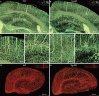

Figure 1.

High-resolution brain atlas providing a global view of the complex vascular network in a C57BL/6 mouse. (A) Representative coronal section showing the cortex (B), hippocampus (C) and thalamus (D), using the whole-brain Nissl-staining method. Boxed areas in A are shown in B, C and D, revealing somata (black) and vessels (white). The stratum oriens (so), strata pyramidale (sp), strata radiatum (sr), cell layers in the hippocampus. Smaller white circles in sr, nerve processes. (E–H) An image of a 200-μm-thick coronal section of the mouse brain reconstructed using volume rendering, with gray levels color-coded. Boxed areas in the cortex F, hippocampus G and thalamus H are shown at a higher magnification. Yellow/green lines, blood vessels; green dots in sp, somata; radial blue lines in sr, dendrites. (I–L) Maximum intensity projection (MIP) of the 400-μm-thick coronal section adjacent to that shown in E, revealing only blood vessels, with the vascular volumetric density coded in color. Boxed areas of the cortex (J), hippocampus (K) and thalamus (L) are shown at a higher magnification.